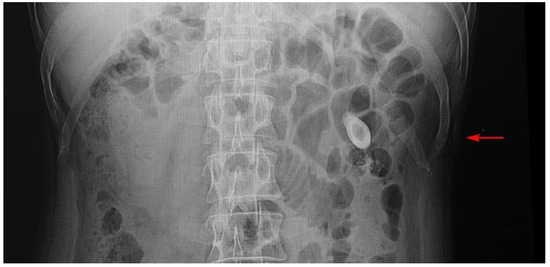

Blood cultures and urine cultures were done and empirical intravenous (IV) piperacillintazobactam was started. His on-admission Creactive protein (CRP) was 231 mg/L and his full blood cell count was 23.1 cells/µL with neutrophil leukocytosis [19.3 cells/µL]. His urine output was normal and the estimated glomerular filtration rate (eGFR) was >90 mL/min. His random and fasting blood sugar was 136 and 104 mg/L, respectively. The hemoglobin A1c was 5.6%. Ultrasound scan of the pelvis revealed leftsided pyelonephritis with pyo-pelvis and left ureteric calculi (Figure 1). Also detected was a moderate hydronephrosis of the left kidney. A nephrostomy tube was inserted to relieve the obstruction which drained pus and was sent to microbiology laboratory in aerobic and anaerobic blood culture bottles for culture and antimicrobial susceptibilities.

Figure 1. X-ray of left renal calculus.